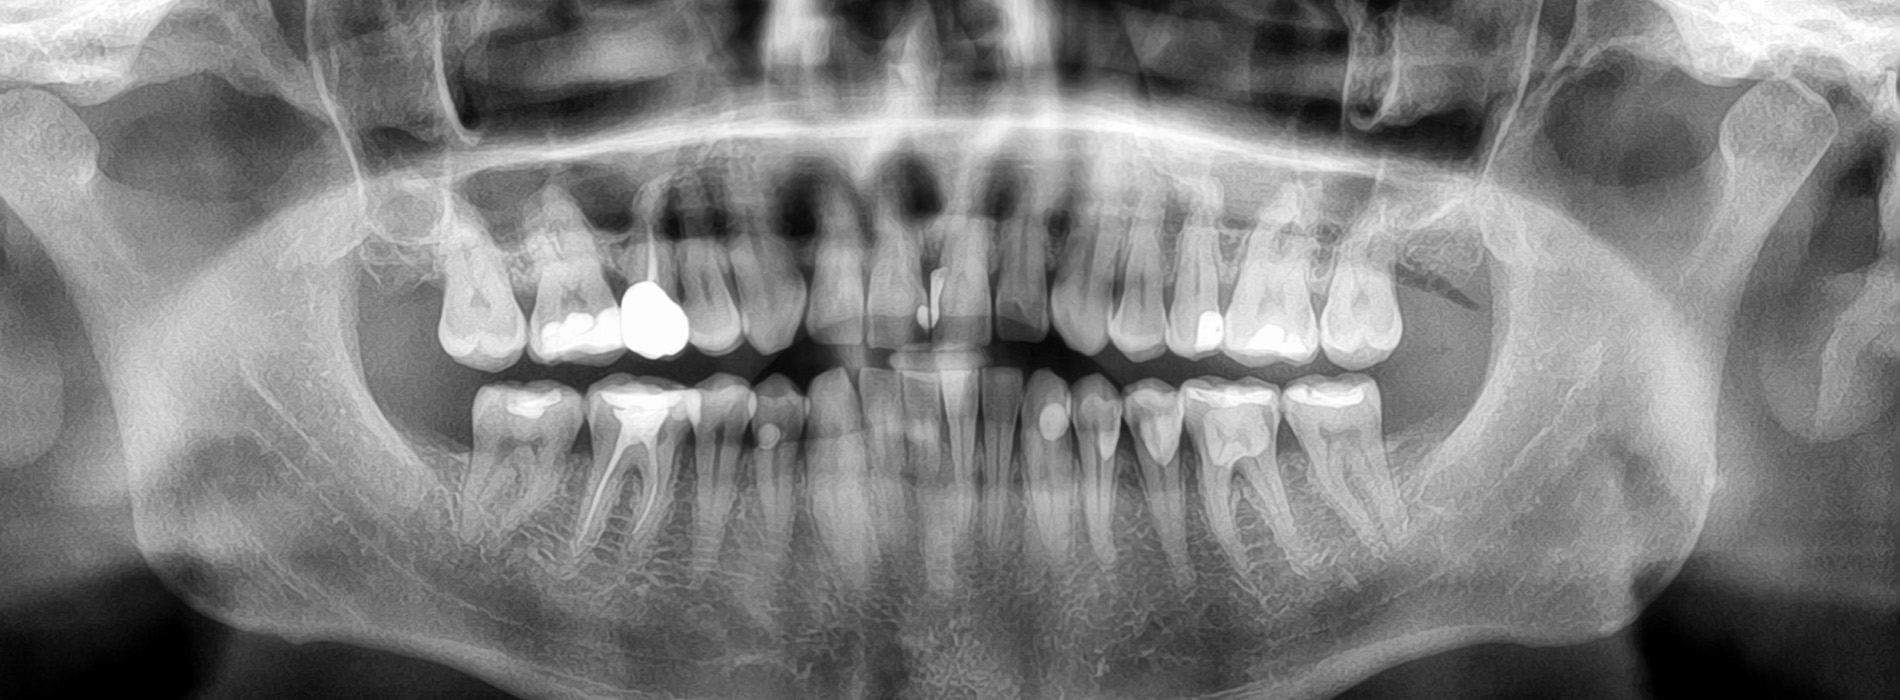

Digital panoramic x-rays are a single, wide-view radiographic image that captures the entire dental arch — upper and lower jaws, all teeth, the temporomandibular joints (TMJ), and the maxillary sinuses — in one sweep. Unlike intraoral bitewing or periapical films that focus on a few teeth at a time, a panoramic image shows relationships across the whole mouth, helping clinicians see how structures align and interact. This bird’s-eye perspective is especially useful when evaluating growth, eruption patterns, and structural anatomy in children and adolescents.

A panoramic x-ray gives clinicians a big-picture view that supports multiple aspects of pediatric dental care and orthodontic planning. It is commonly used to monitor the position of permanent teeth before, during, and after eruption; to evaluate the presence of supernumerary (extra) or missing teeth; and to identify abnormalities in jaw growth or tooth formation. This makes panoramics a frequent choice during initial orthodontic assessments and routine developmental checkups.

Because panoramic images show both jaws and the surrounding skeletal structures, they assist in detecting large-scale conditions such as cysts, tumors, or significant bone changes that would be difficult to appreciate on small intraoral films. For orthodontists and pediatric dentists, panoramics help map the timing of interventions and coordinate care between specialties by showing how teeth and jaws relate to one another.

Interpreting a panoramic x-ray requires clinical training and experience. The image provides clues about tooth position, root development, jaw symmetry, and anatomical landmarks, but it also has inherent limitations: distortion and overlapping structures can obscure fine details. That’s why dentists correlate panoramic findings with a clinical exam and, when needed, targeted intraoral radiographs or three-dimensional imaging for precise measurements.

Digital panoramic X-rays are single, wide-view radiographic images that capture the upper and lower jaws, all erupted and developing teeth, the temporomandibular joints and adjacent sinus areas in one sweep. The image is produced by a rotating arm and a digital sensor outside the mouth, which creates a comprehensive, two-dimensional representation of the entire dental arch. Because the file is digital, clinicians can view, enlarge and enhance the image immediately to aid diagnosis and discussion with caregivers.

Panoramics provide a bird’s-eye perspective that is especially useful for assessing growth, eruption patterns and large-scale structural relationships in pediatric patients. They are a diagnostic starting point rather than a replacement for more focused imaging when fine detail is required. Used appropriately, panoramic X-rays help guide further evaluation and treatment planning.

Panoramic X-rays can reveal issues that are not visible during a visual exam, including unerupted or impacted teeth, supernumerary teeth, abnormal tooth development and large cysts or other jaw lesions. They also show the relationship between the jaws and teeth, which is helpful for detecting asymmetries, growth disturbances and some types of trauma that affect bone structure. These findings often guide timing of interventions and the need for specialist referral.

While panoramics are excellent for broad screening, they have limitations for detecting small cavities, early bone loss or subtle root fractures due to overlap and reduced resolution compared with intraoral images. Dentists correlate panoramic findings with a clinical exam and order targeted radiographs or CBCT scans when finer detail is required. This layered approach ensures thorough evaluation while minimizing unnecessary exposure.